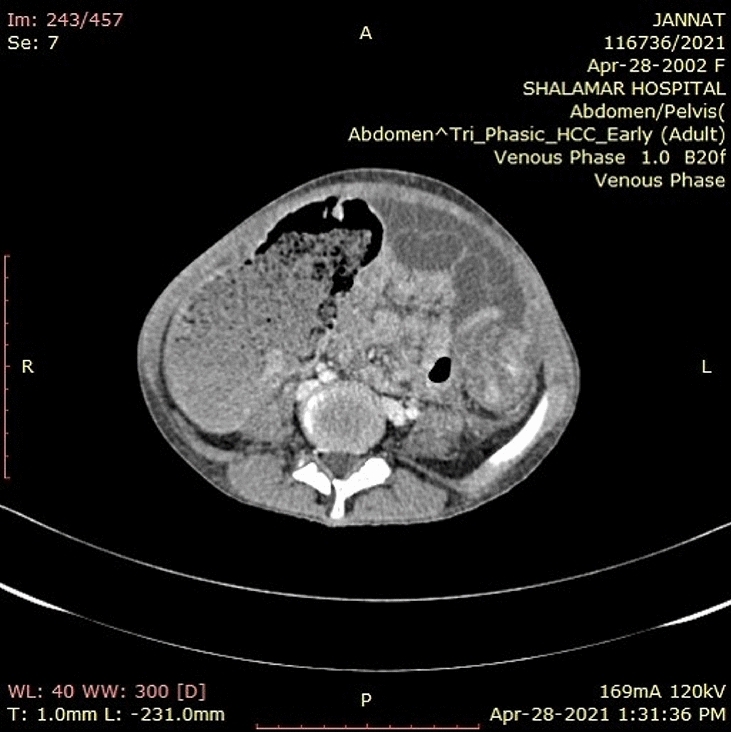

Fig. 1 Hernia sac measurements for calculating VIH (Left to right: axial, sagittal, coronal)